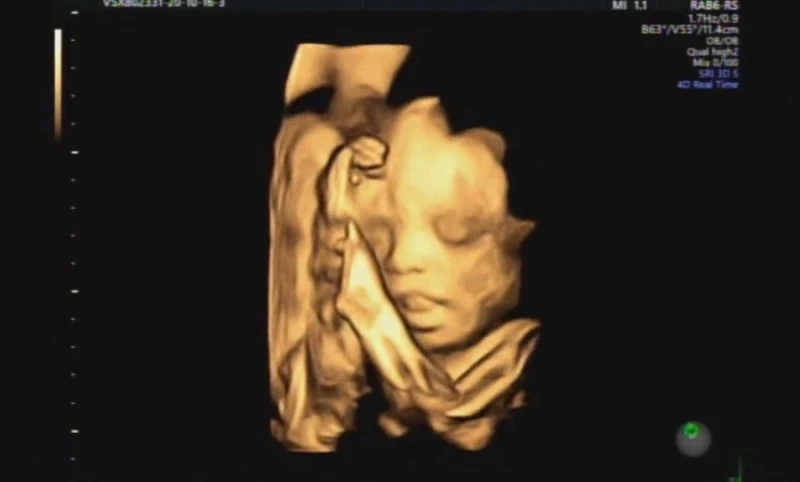

그러던 중 임신 26주차쯤 되었을 때, 친정어머니와 입체초음파를 보러 가기로 했다.

태아의 얼굴을 어느 정도 선명히 볼 수 있다는 입체초음파.. 남편을 닮았을지, 나를 닮았을지 조마조마 궁금해하며 초음파 화면을 들여다봤다.

그런데 이상하게도, 아기가 입을 계속 벌리고 있었다.

세브란스 담당 교수님이 오랜 시간 초음파를 들여다보시다가 찾아낸 시온이의 종양.

대략적인 사이즈가 4cm 정도 된다고 하셨다.

작은 아기 얼굴에 4cm라면... 얼마나 큰 종양인 것인가..